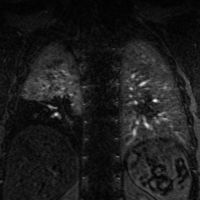

Thank you for your interest in cardiovascular imaging at the University of Wisconsin School of Medicine and Public Health, Department of Radiology. The Cardiovascular Imaging Section has long provided innovative, advanced clinical care in non-invasive cardiovascular imaging, including cardiac magnetic resonance imaging (MRI), magnetic resonance angiography (MRA), cardiac and coronary computed tomography (CCTA), and computed tomography angiography (CTA).

The volume of clinical studies has grown continuously and we now perform over 5000 non-invasive cardiovascular CT and MR studies each year. The members of our section are very active and renowned locally, nationally, and internationally with over 550 peer-reviewed publications, 30 book chapters, 1200 scientific presentations, and 50 patents. Time-resolved contrast-enhanced MRA (TRICKs), pulmonary MRA for pulmonary embolism, non-contrast-enhanced MRA, four-dimensional (4D) flow MRI, low-dose CTA and CCTA, and 3D printing are just a few examples of the innovations developed by our group that have had a significant impact on clinical care locally and beyond.